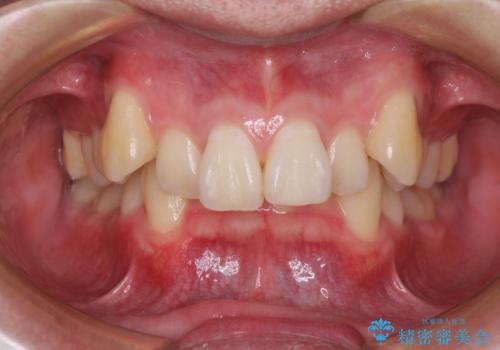

[ マウスピース矯正 ] がたがたした歯並びを治したい

担当医 大元洋佑

![[ マウスピース矯正 ] がたがたした歯並びを治したいの症例 治療前](https://seimitsushinbi.jp/wp/wp-content/uploads/2024/04/IMG_0106-500x350.jpg?v=1711951424)

![[ マウスピース矯正 ] がたがたした歯並びを治したいの症例 治療後](https://seimitsushinbi.jp/wp/wp-content/uploads/2024/04/46939b7482334672d3a091da1562afec-500x350.jpg?v=1711951403)